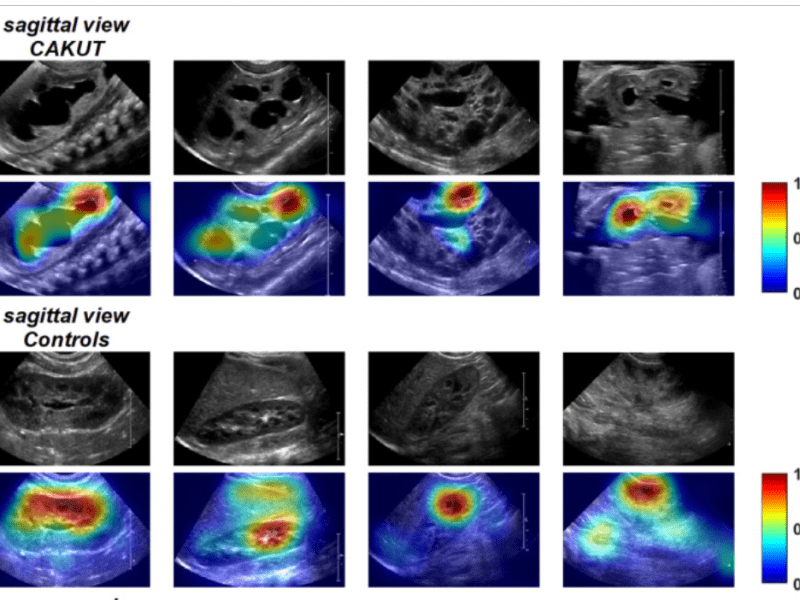

PUV Article DOI https://doi.org/10.1016/j.urology.2020.05.019 Objective To diagnose children with PUV AI Approach CNN with transfer learning Data Source(s) Institutional series (157 children: 3504sagittal ultrasounds, 2558 transverse ultrasounds) Model Input Sagittal and/or transverse features of renal ultrasounds Model Outcome PUV Model Metrics AUROC = 0.96, accuracy = 93% Model Usability https://github.com/YS181818/CAKUT_diagnosis/tree/master AI = Artificial intelligence, AUROC…